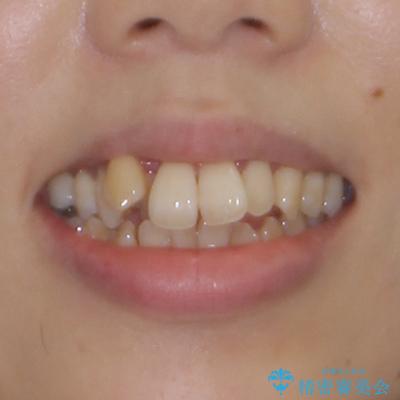

- 前歯のデコボコと唇の閉じにくさを気にして来院された患者様です。

デコボコが強い上に、口元の突出感も気にしていたため、上下左右の小臼歯4本を抜歯して、ワイヤー装置にて矯正治療を行うこととしました。

それでも当初とは比べものにならないほど、綺麗な歯列に仕上げることができました。